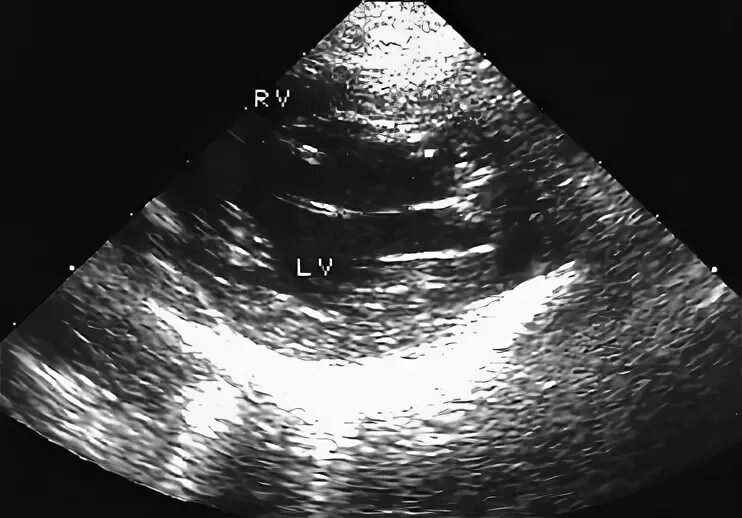

Марс дхлж у ребенка